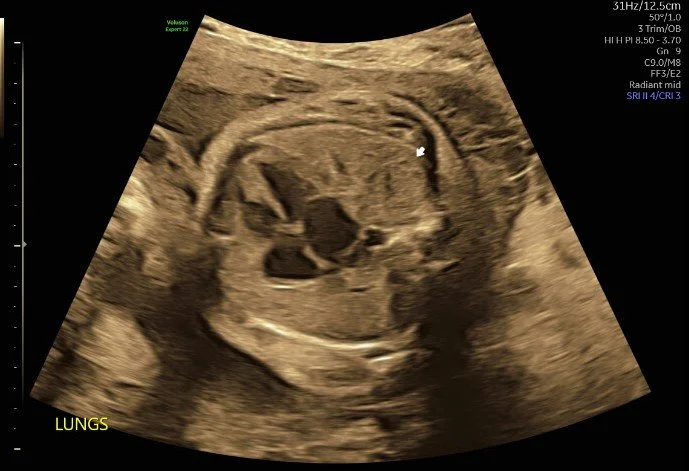

Patient was referred to MFM office for intrauterine growth restriction and incomplete anatomy views from her primary OB office. Upon ultrasound examination, an absent left kidney was quickly suspected, then later located superior to the stomach. Two weeks later, the patient returned for an amniocentesis and Dopplers.

Patient was sent for an MRI due to a possible ectopic kidney or congenital diaphragmatic hernia based on ultrasound exam. The MRI confirmed a posterior congenital diaphragmatic hernia containing the left kidney, adrenal, and bowel.